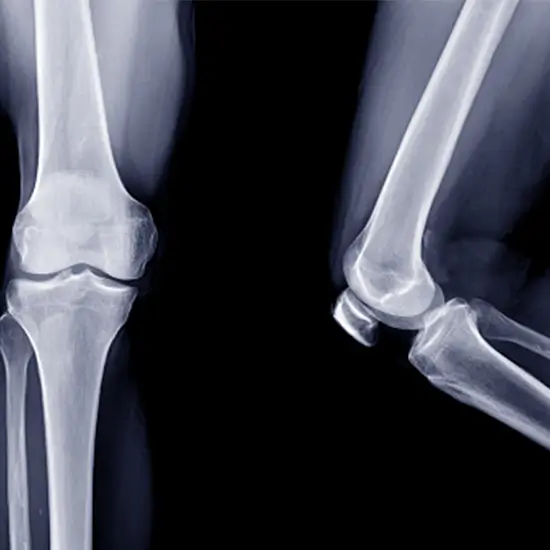

x-ray right patella lat and ap

X-Ray Right Patella LAT & AP

What is an X-ray Right Patella LA AP Views Test?

The patella test utilizes an X-ray to visualize the knee cap. Patella is a circular-triangular bone that surrounds the knee joint and articulates with the lower end of the femur (thigh bone).